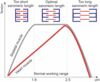

Describe Starling’s effect

To increase load, the heart automatically reacts with extra work

without hormonal/neuronal factors

Describe the heart’s work load status during rest

The heart is working in the lower range of its total working capacities

This is ensured by parasympathetic predominance

A decrease of parasympathetic activity may cause…

An increase in the mechanical performance of the heart